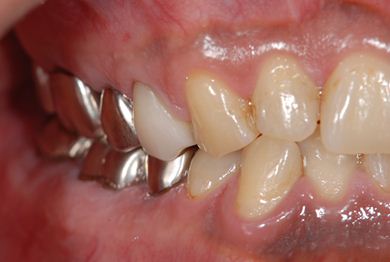

インプラントの症例写真 IMPLANT

インプラント治療+セラミック治療+歯肉歯槽骨整形術

| 性別/年齢 | 男性 / 47歳 | ||||||||||||||||||||||||||||||||

| 主訴 | 悪いところの治療と、歯をきれいにしたい。 | ||||||||||||||||||||||||||||||||

| 治療方針 | 右下奥、保存不能な歯を抜歯し、インプラント治療にて、機能的・審美的回復を行う。 | ||||||||||||||||||||||||||||||||

| 治療内容 | インプラント2本、メタルボンドセラミッククラウン9本(メタルボンド用土台6本)、ハイブリッドセラミッククラウン2本(セラミック用土台2本)、ハイブリッドセラミックインレー5本、歯肉歯槽骨整形術 | ||||||||||||||||||||||||||||||||